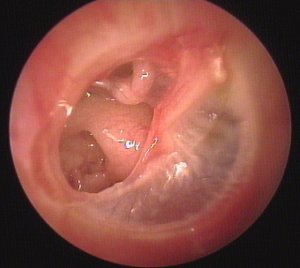

Abnormal tympanic membranes |

![]() |